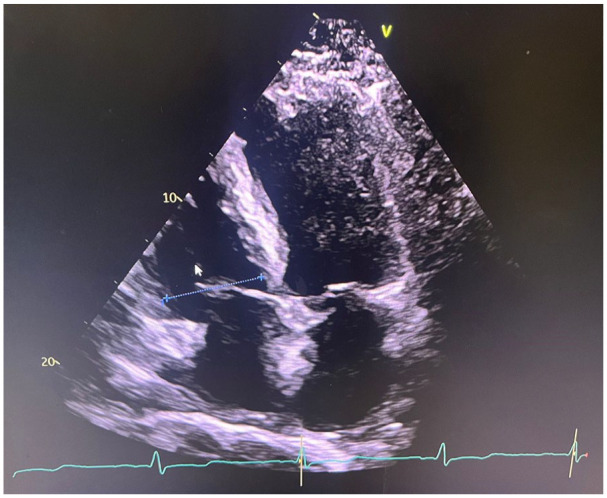

Cardiac amyloidosis (CA) is a rare disorder caused by the deposition of abnormal proteins called amyloid in the myocardium, leading to dysfunction. The 2 most common forms of amyloidosis are AL (light chain) and ATTR (transthyretin). Diagnosing amyloidosis is challenging, especially in its early stages, due to its nonspecific symptoms and overlap with other conditions. Recent studies suggest that the incidence of wild-type transthyretin amyloidosis is rising, likely due to improved diagnostic techniques and an aging population. We present the case of a 72-year-old male with lower extremity edema, progressive shortness of breath, and worsening renal function. He had a significant medical history, including hypertension, small lymphocytic lymphoma, coronary artery disease, diabetes, and chronic kidney disease. Physical examination revealed orthostatic hypotension and peripheral neuropathy. Imaging showed restrictive cardiomyopathy with reduced ejection fraction. Laboratory tests confirmed anemia and proteinuria, while a bone marrow biopsy ruled out AL amyloidosis. A Tc-99m pyrophosphate scan confirmed the diagnosis of ATTR CA. ATTR often presents with multi-organ involvement, complicating diagnosis. This patient's coexisting conditions, including orthostatic hypotension and renal failure, may have been aggravated by amyloidosis. Misdiagnosis between AL and ATTR can lead to inappropriate treatments, making accurate diagnosis crucial. ATTR requires transthyretin stabilizers and symptom management, while AL needs chemotherapy. Treatment of amyloidosis must be individualized, as autonomic dysfunction, arrhythmias, and renal involvement require careful management. Early diagnosis and differentiation are essential for appropriate treatment and improved outcomes in patients with multi-organ involvement.